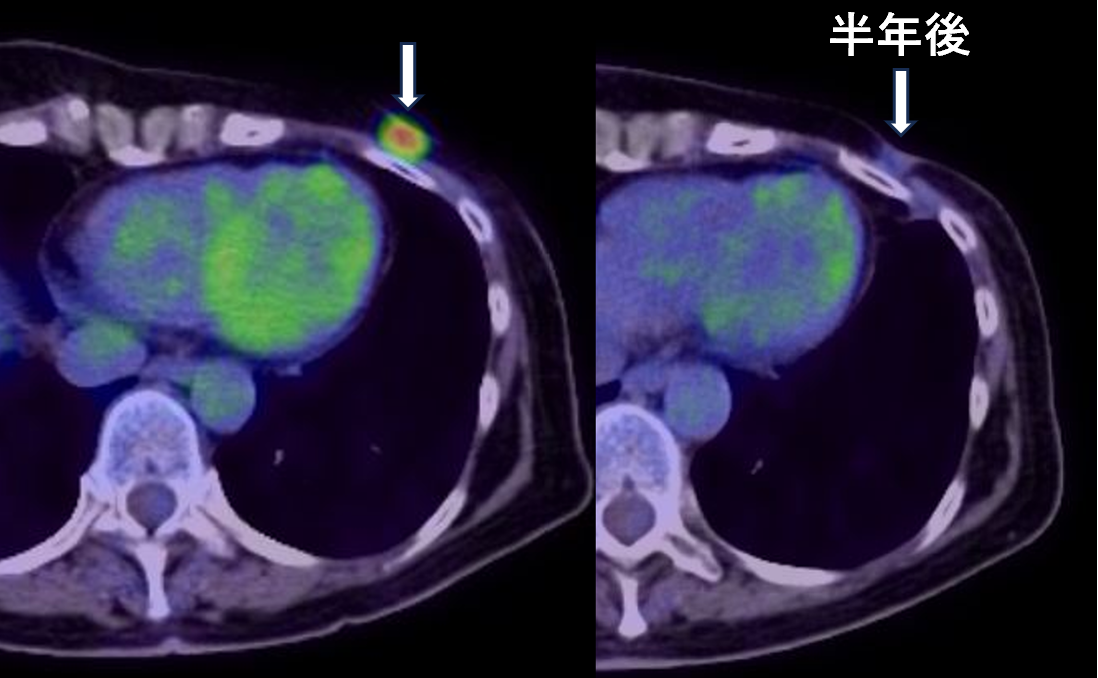

【代引き不可】 imgrc0109619801.jpg 臨床医学